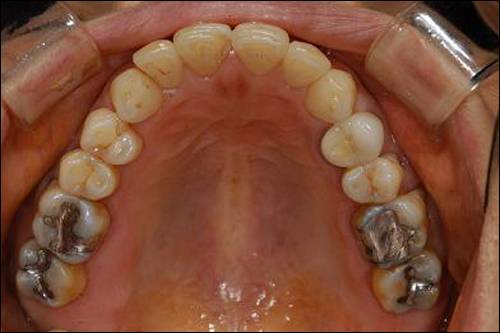

제일 먼저 살펴볼 아말감의 최대 장점은 역시 저렴함에 있다고 얘기하겠다. 그 밖의 장점으로는 치아의 상아질과 강도가 비슷해서 닳는 속도가 흡사하다는 점, 부식 시 발생하는 부산물에 의해 치면과의 사이가 잘 막혀서 미세누출이 적다는 점, 상대적으로 술자의 실력이나 환경의 영향을 적게 받는 점 등이다.

다음으로 아말감 자체의 색이 좋지 않고 수복재 주변 치아를 변색시키기 때문에 비심미적이라는 단점 역시 가지고 있다. 마지막으로 인접치와 닿은 부분에서는 그 성능이 현저하게 떨어진다.

좋은 장기 예후를 위해서는 꾸준한 연마가 필요한 것 역시 아말감의 단점이다. 아말감은 낮은 가격에 비해 비교적 양호한 성능을 보이는 재료이지만 어떤 케이스에서도 1등이 될 수는 없다. 자동차에 비유하면 가격 대비 성능이 뛰어난 경차쯤으로 생각하면 이해가 빠를 것이다.